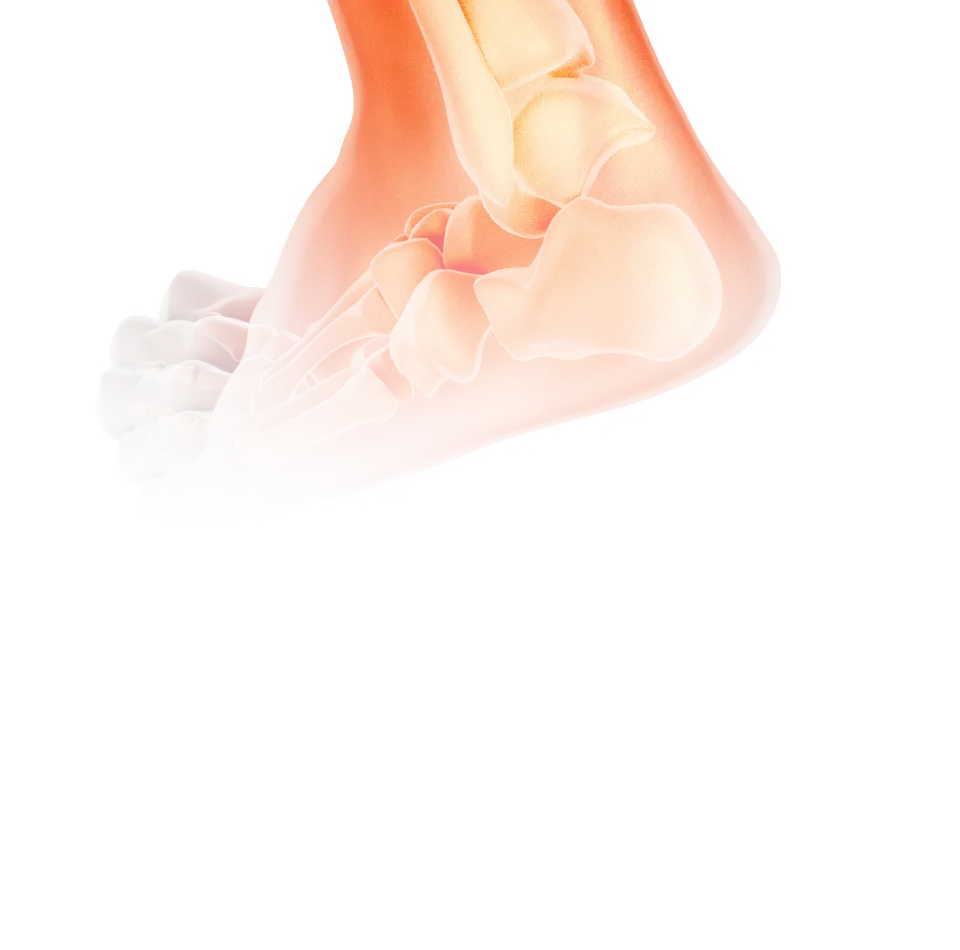

아킬레스건염

아킬레스건은 걷거나 뛸 때 매우 중요한 역할을 하는 힘줄이며,

이 힘줄을 둘러싸고 있는 막에 생기는 염증이 생기는 질환을 아킬레스건염이라 합니다.

원인

• 발바닥이 평평한 평발, 요족일 경우

• 딱딱한 바닥에서 발바닥에 충격을 줬을 때

• 과체중이거나 장시간 서 있는 경우

• 하이힐 착용으로 족저근막에 무리

• 중년 이후 발바닥 근육의 힘이 약화

• 무리한 스포츠 활동